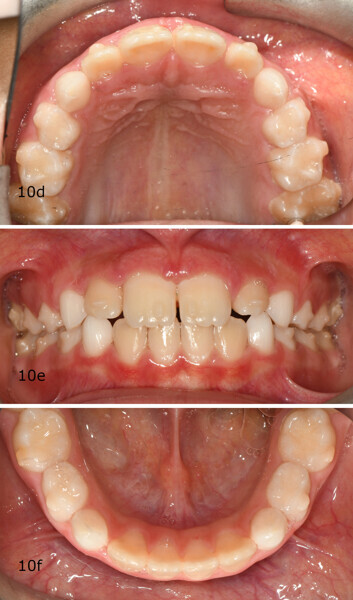

The 8-year-old male patient presented with a diastema between teeth #11 and 21 and non-eruption of teeth #12 and 22 (Fig. 1). The patient underwent a thorough orthodontic examination, including intra-oral photographs, extra-oral photographs, cephalometric radiography of the skull with cephalometric tracing, dental panoramic tomograms, impressions by intra-oral scanning, and functional and phonetic tests. Intra-oral examination (Fig. 2) and pattern analysis showed a Class I molar and canine relationship and contraction of the maxillary arch, displaced pre-contact between teeth #63 and 73, a 3.7 mm diastema between teeth #11 and 21, a mandibular midline deviation to the left, a maxillary midline to the right, and an open bite (−1.5 mm).

After 18 months of therapy, a case reassessment was carried out to verify that the goals had all been achieved (Fig. 8). Comparison of extra-oral photographs at the start of treatment (T0) and end of treatment (T1; Fig. 9) showed that excellent balance of the patient’s face had been achieved with a regular, symmetrical smile. Comparison of the intra-oral photographs (Fig. 10) and models (Fig. 11) also showed wider and more harmonious arch forms, closure of the anterior diastema, closure of the open bite and recentring of the mandibular midline. Excellent gingival trophism had also appeared.